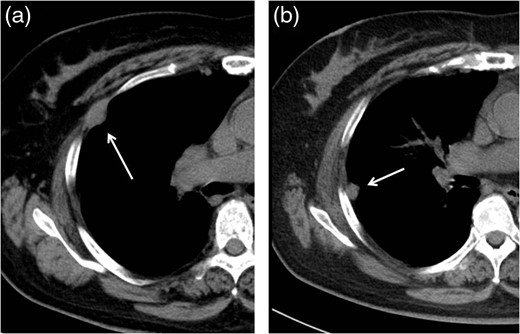

Follow-up CT performed 36 months after the operation revealed two pleural tumors located near the second and third ports (Fig. 2a and b). We suspected the pleural recurrence of thymoma and performed a second operation. Initially, the operation was performed only by VATS with three ports. After removing the severe adhesion between the lung and chest wall, we were able to identify the two tumors. As with the extrapleural tumor, the tumors arose from the intercostal space. Their surfaces were covered with parietal pleura with partial irregularity (Fig. 3). There were no other recurrent findings in the thoracic cavity. Given these findings, we diagnosed these tumors as port-site implantations after the first VATS.

Follow-up CT at 36 months after the operation revealed two pleural tumors locating at the second (a) and third (b) ports used in the VATS operation.

In the operative findings, the tumors were found to have arisen from the intercostal space, and their surfaces were covered with parietal pleura with partial irregularity.